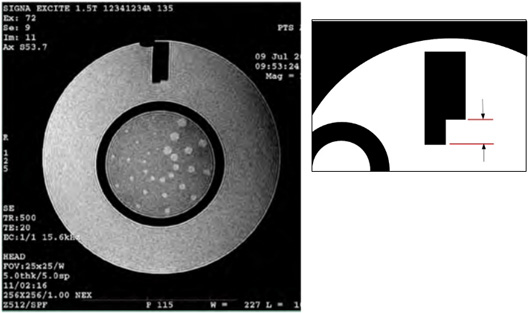

View the resulting ACR sagittal localizer image and verify that the phantom appears as below.

Figure 8. Example for ACR Sagittal Localizer Series